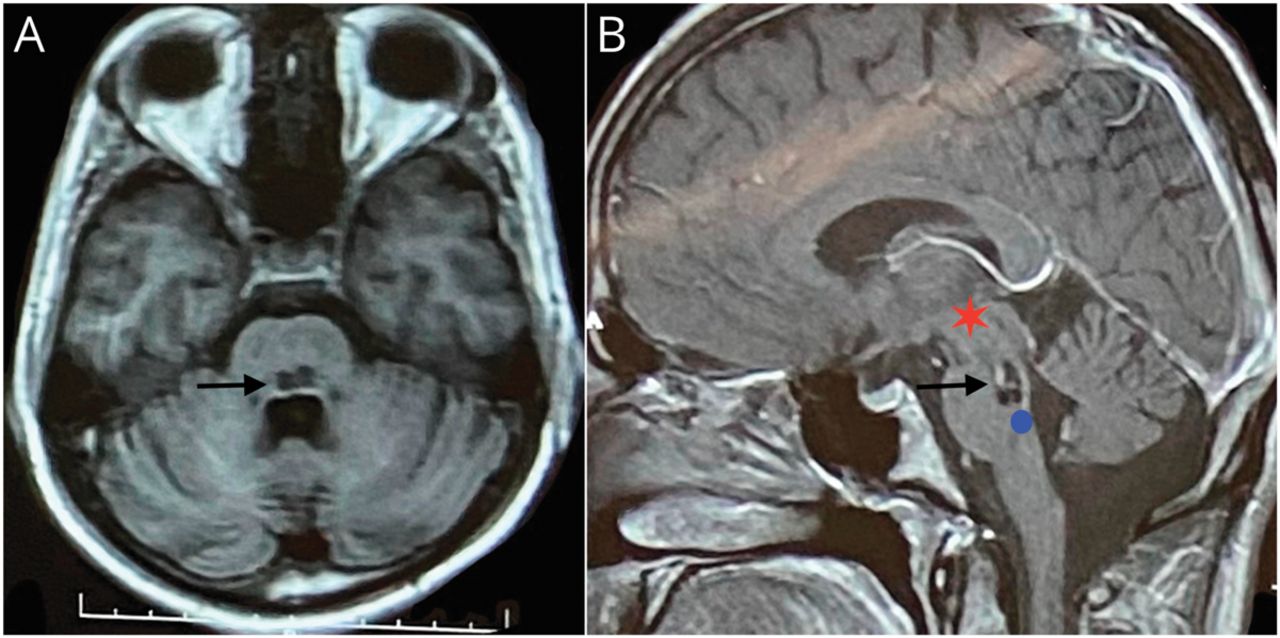

(A) t1加权轴向MRI序列显示脑桥背侧低信号病变(黑色箭头标记)。(B) T1W+C矢状面MRI序列显示脑桥后背交界处病变(黑色箭头标记),对比增强微弱。红星代表riMLF,其中有垂直跃动的兴奋性爆发神经元,桥背的蓝色圆圈接近中线外展核水平中缝间核的全顶细胞位置。rimf和全顶神经元之间的连接被破坏,导致反向跳动。riMLF =内侧纵束吻侧间质核。